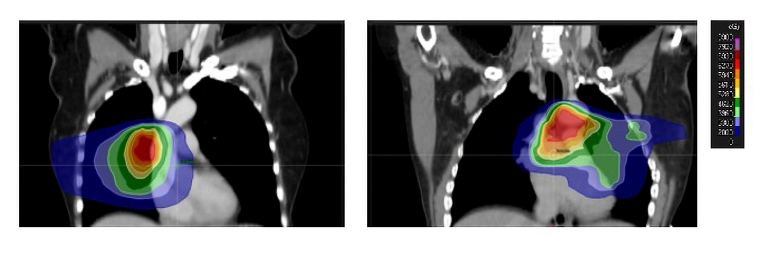

In contrast to the long-standing belief that the survival of patients with lung or oesophageal cancer was too short for RIHD to develop, new research has increased awareness of the link between heart dose and cardiac mortality in these patients. Attempts at escalating the dose of radiotherapy to improve survival have been disappointing and this may be due, in part, to increased heart dose. The radiation dose received by the heart in patients with lung and oesophageal cancer depends on the tumour stage and location. For example, large tumours in the middle and lower lobes of the lung or the lower oesophagus and those involving hilar and inferior mediastinal nodes will result in greater heart dose (Figure 3). Patients receiving radiotherapy to a lower oesophageal tumour have been shown to have an increased risk of cardiac death [11].

254_Aznar_Figure3-Radiotherapy and its consequences what the cardiologist should know.jpg